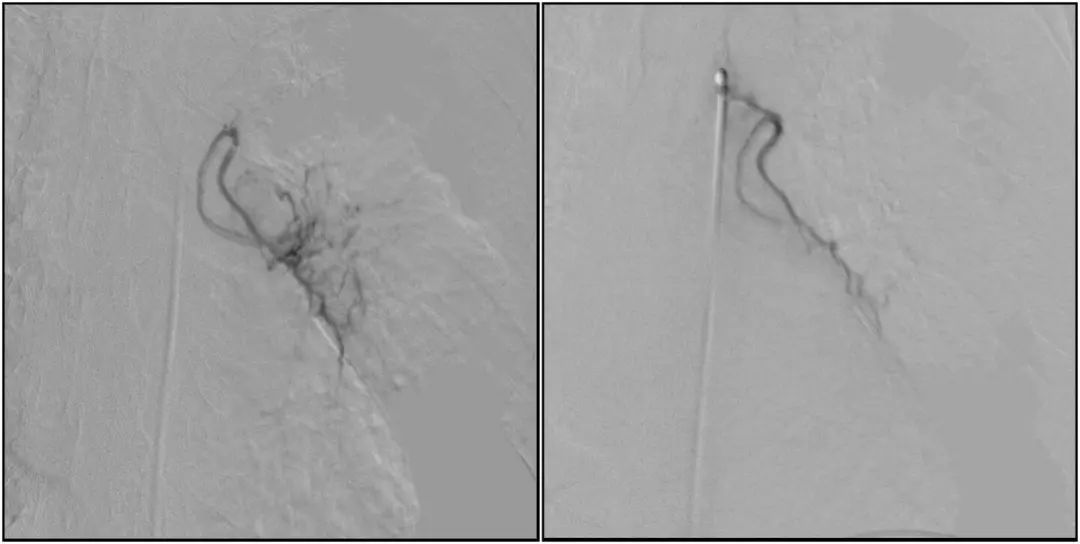

在微导丝的配合下,先后分别超选择①至3支左侧支气管动脉肿瘤供血动脉,经微导管推注栓塞微粒球栓塞肿瘤动脉。栓塞结束后,再次用移动式平板介入中C做造影检查,见肿瘤染色消失。

术前术后对比影像